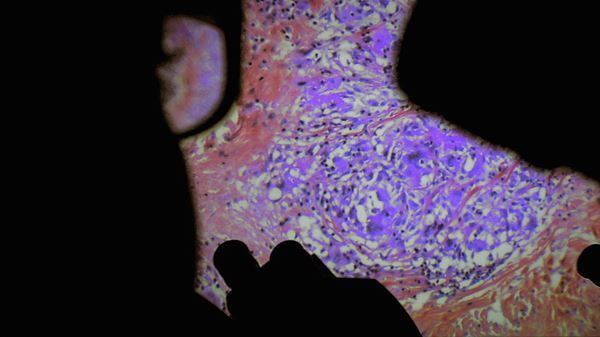

上映されるのは、実際の外科手術を医師の視点で撮影し、人間の体の神秘に迫るショッキングかつ感動的な異色のドキュメンタリー『人体の構造について(原題)』。『リヴァイアサン』『カニバ パリ人肉事件38年目の真実』といった話題作を共に手がけてきた、ルーシァン・キャステーヌ=テイラーとヴェレナ・パラヴェルの人類学者コンビが贈る衝撃作だ。普段なかなか目にすることのできないオペの様子を通じて、我々人間の体を構成する様々な臓器の神秘や儚さを映し出すと同時に、強烈なインパクトを残す作品となっている。

『人体の構造について(原題)』ビジュアル